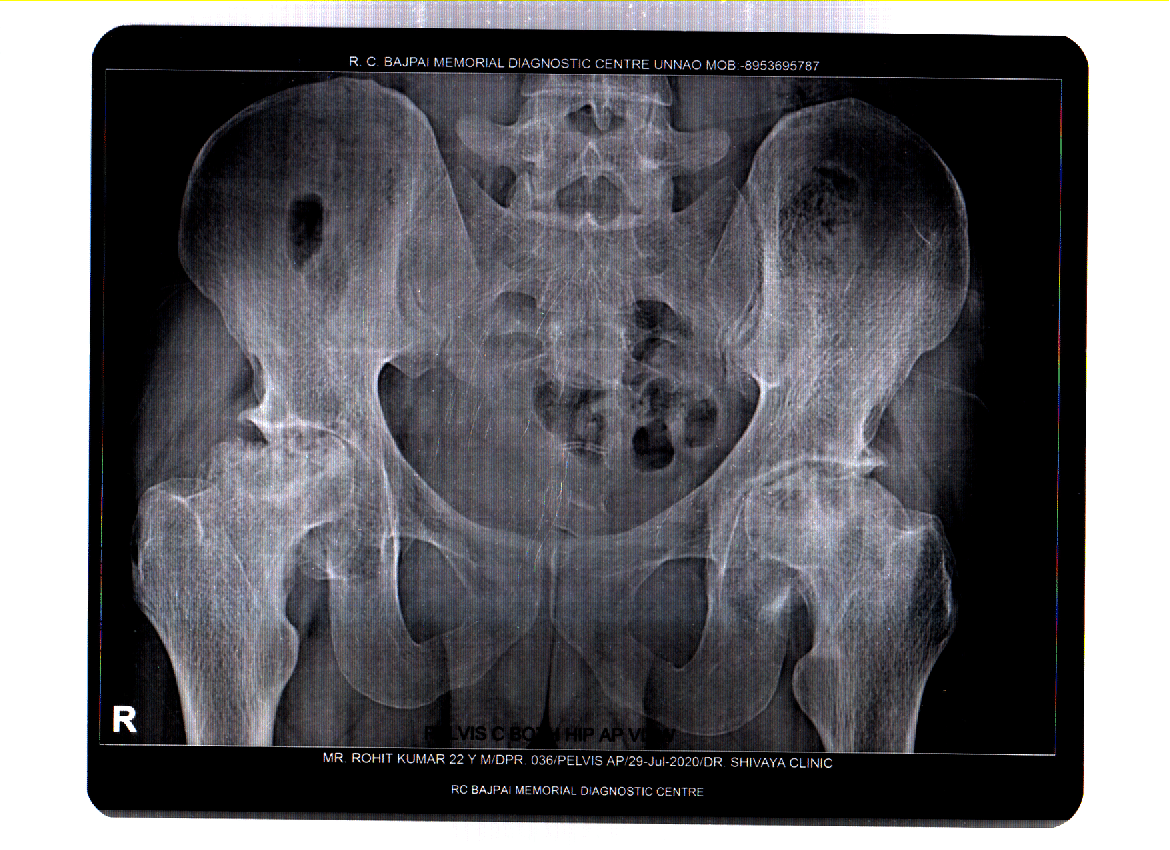

Avascular necrosis of the femoral heads X Rays Case Studies CTisus Is Avascular Necrosis Urgent avascular necrosis (avn) is a disease of the bone. they can reveal bone changes that occur in the later stages of avascular necrosis. it is also known as avascular necrosis, aseptic necrosis, and ischemic bone necrosis. It commonly affects the hip joint. avascular necrosis is a disease that results from the temporary or permanent loss of. Is Avascular Necrosis Urgent.

Avascular necrosis of the hip Image Is Avascular Necrosis Urgent Necrosis is a general term that means a cell has died. avascular necrosis is a painful condition that can significantly affect your quality of life. It commonly affects the hip joint. avascular necrosis occurs when there is a disruption in blood flow to part of a bone, causing the bone tissue to die. avascular necrosis (avn) is. Is Avascular Necrosis Urgent.